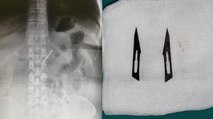

ANKARA - Başkent'te karın ağrısı şikayetiyle hastaneye başvuran 46 yaşındaki kadının midesinde 2 adet neşter tespit edildi. Gerçekleştirilen başarı operasyon ile neşterler vücudundan çıkarılan kadının sağlık durumunun iyi olduğu öğrenildi.

Sağlık Bilimleri Üniversitesi Ankara Atatürk Sanatoryum Eğitim ve Araştırma Hastanesi'ne mide ve karın bölgesinde aşırı ağrı şikayeti ile müracaat eden 46 yaşındaki D.E.'nin yapılan tahlil, tetkik ve çeşitli görüntülemelerden sonra bağırsak kısmında 2 adet neşter olduğu tespit edildi. Genel cerrahi kliniği tarafından zorlu bir ameliyat sonrasında neşterler kadının vücudundan çıkarıldı. Haber